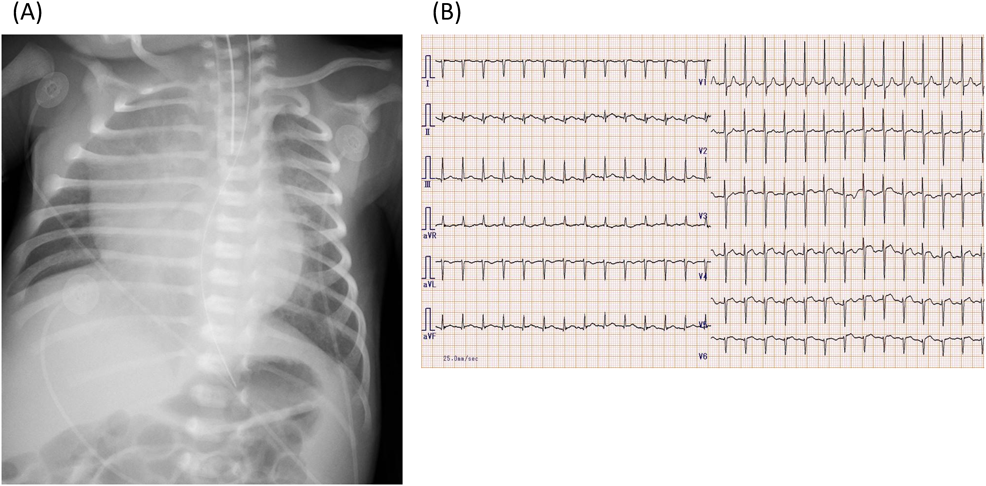

日齢9に行った血液検査ではCK 569 U/L,トロポニンI 4813.6 pg/mLと心筋逸脱酵素の上昇ならびにBNP 4131.4 pg/mL, IgM 204 mg/dLを認めた(Table 1).胸部X線写真(Fig. 1)では,心胸郭比67%と心拡大を認めた.12誘導心電図(Fig. 1)では前胸部誘導にST-T変化を認めた.心臓超音波検査では左室拡張末期径26.3 mmと左室拡大を認め,左室駆出分画(LVEF)は33%と著明に低下していた.Moderate MR, moderate TRを認めた.三尖弁輪収縮期移動距離は3 mmと低下しており,三尖弁圧較差(TRPG)59 mmHg程度と高値で肺高血圧症(PH)を認めた.肺動脈狭窄や肺静脈狭窄は認めず,心嚢液は少量貯留していた.

Fig. 1 Chest X-ray (A) and Electrocardiography (B) on admission